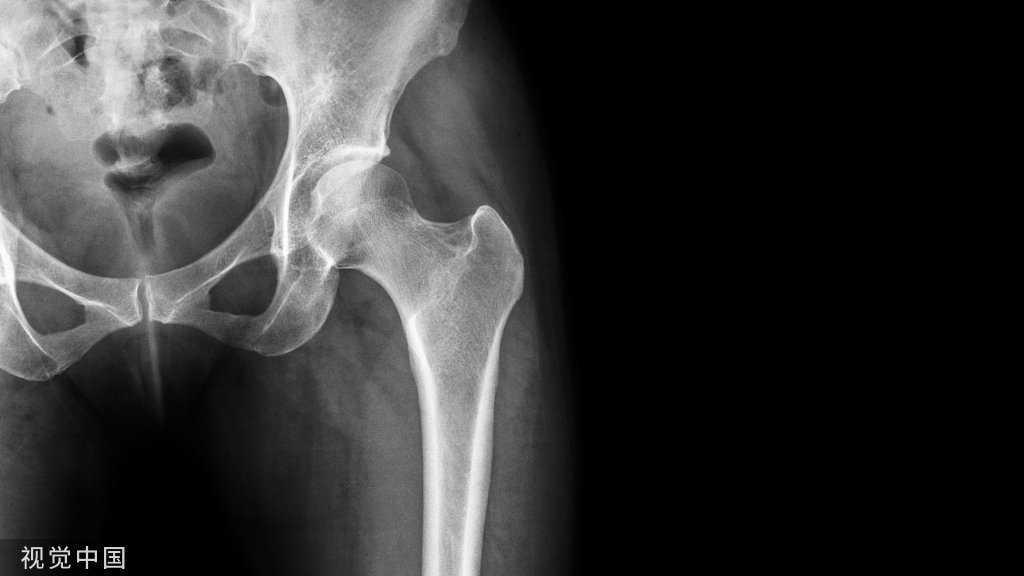

儿童股骨干骨折骨骨折

双腿悬吊牵引法

适用于5岁以下儿童有移位的股骨干骨折。伤侧、健侧同时用胶布皮牵引,双腿同时悬吊,臀部离开床面,牵引重量健侧比伤侧稍轻,为了防止成角畸形,可用夹板外固定。

水平皮肤牵引法

适用于5~12岁儿童有移位的股骨干骨折。股骨干中、上段横断、重叠骨折,在麻醉下进行整复、夹板外固定后,伤肢水平牵引,或用托马氏架牵引,重量2~3公斤。股骨上1/3骨折,伤肢应在充分屈髋,外展位牵引。股骨下1/3骨折,要尽量屈膝,以松弛膝后方的关节囊和腓肠肌,减少骨折远端向后侧的移位。胫、腓骨骨干双骨折